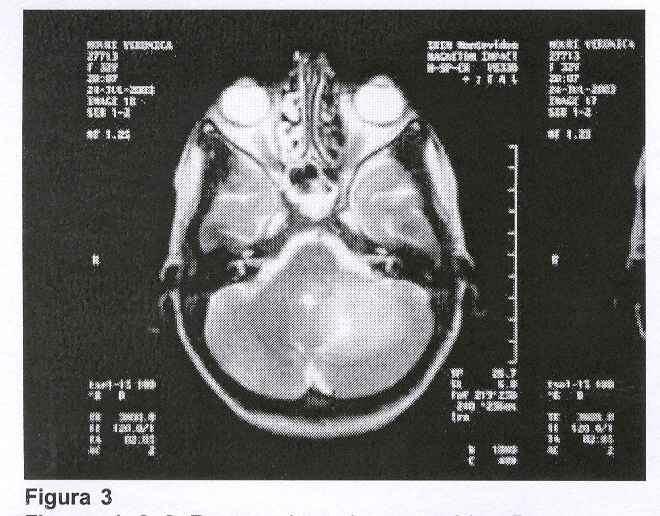

Con el planteo clínico de lesión ocupante de fosa posterior se solicitaron exámenes imagenológicos. La TAC, que fue realizada sin contraste, mostró una ligera atrofia cortical frontal bilateral sin otras anormalidades, por lo que se solicitó resonancia magnética de cráneo que mostró: "Proceso patológico en hemisferio cerebeloso izquierdo a nivel córtico-subcortical que se extiende a pedúnculos cerebelosos. Lesión de límites difusos con señal alta e inhomogénea en T2. Ligero efecto de masa con compresión del IV ventrículo. Aumento de su señal post contraste intravenoso persistiendo un área de señal baja a nivel central".